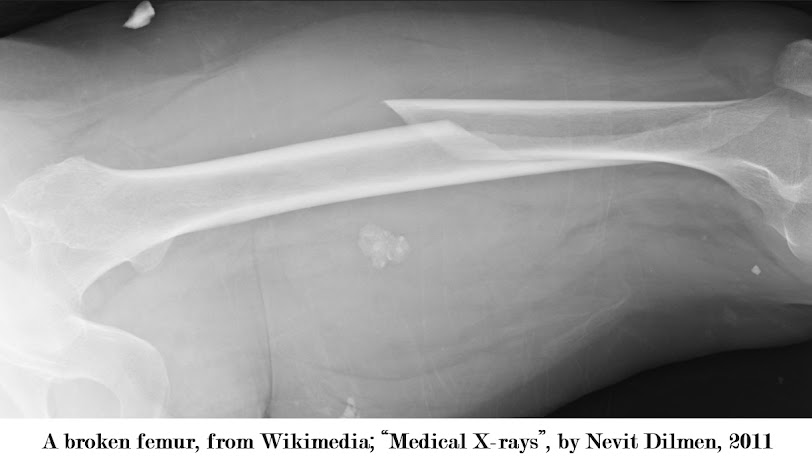

A

fall from a great height or a high-speed car collision can result in a femoral

shaft fracture, which is a severe injury.

A fractured femur, also known as a thighbone, is a bad break that

requires serious and immediate attention.

Wikimedia; “Medical

X-rays”, by Nevit Dilmen, 2011, https://commons.wikimedia.org/wiki/File:Medical_X-Ray_imaging_IYN05_nevit.jpg,

accessed April 5, 2024